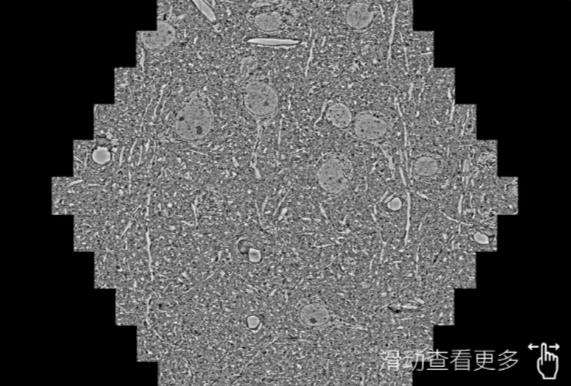

鼠脑切片。左图使用七台河蔡司七台河扫描电镜MultiSEM706对165μmx143pm面积区域成像,耗时仅需1.5秒。右图为鼠脑切片中30μm区域放大效果。样品由芝加哥大学B.Kasthuri提供。

使用蔡司高速七台河扫描电镜MultiSEM对1mm²人脑皮层组织进行高分辨成像,并对其中的各种细胞结构进行三维重构分析。左图展示了2x3mm²组织平面中锥体神经元的三维重构效果。右图显示了局部体积神经元三维重构。图像由哈佛大学chtman实验室提供,渲染图由D. Berger 制作。